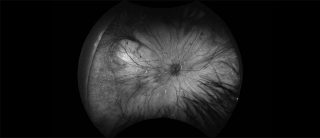

Peripheral retinal imaging uses ultra-widefield retinal cameras to capture images of the outer areas of the retina. These systems allow clinicians to visualise and document the peripheral retina, which can be important for detecting and monitoring conditions that may not be visible in standard central images.

The type of retinal camera used depends on the patient’s suspected or confirmed diagnosis. Different eye conditions affect different areas of the retina, so selecting the most appropriate imaging system helps clinicians obtain the most useful information.

In contrast, patients with diabetic retinopathy often require widefield or ultra-widefield imaging. This allows clinicians to examine the peripheral retina and check for signs such as peripheral ischaemia, new blood vessel growth, or other changes that may not be visible in standard central images.